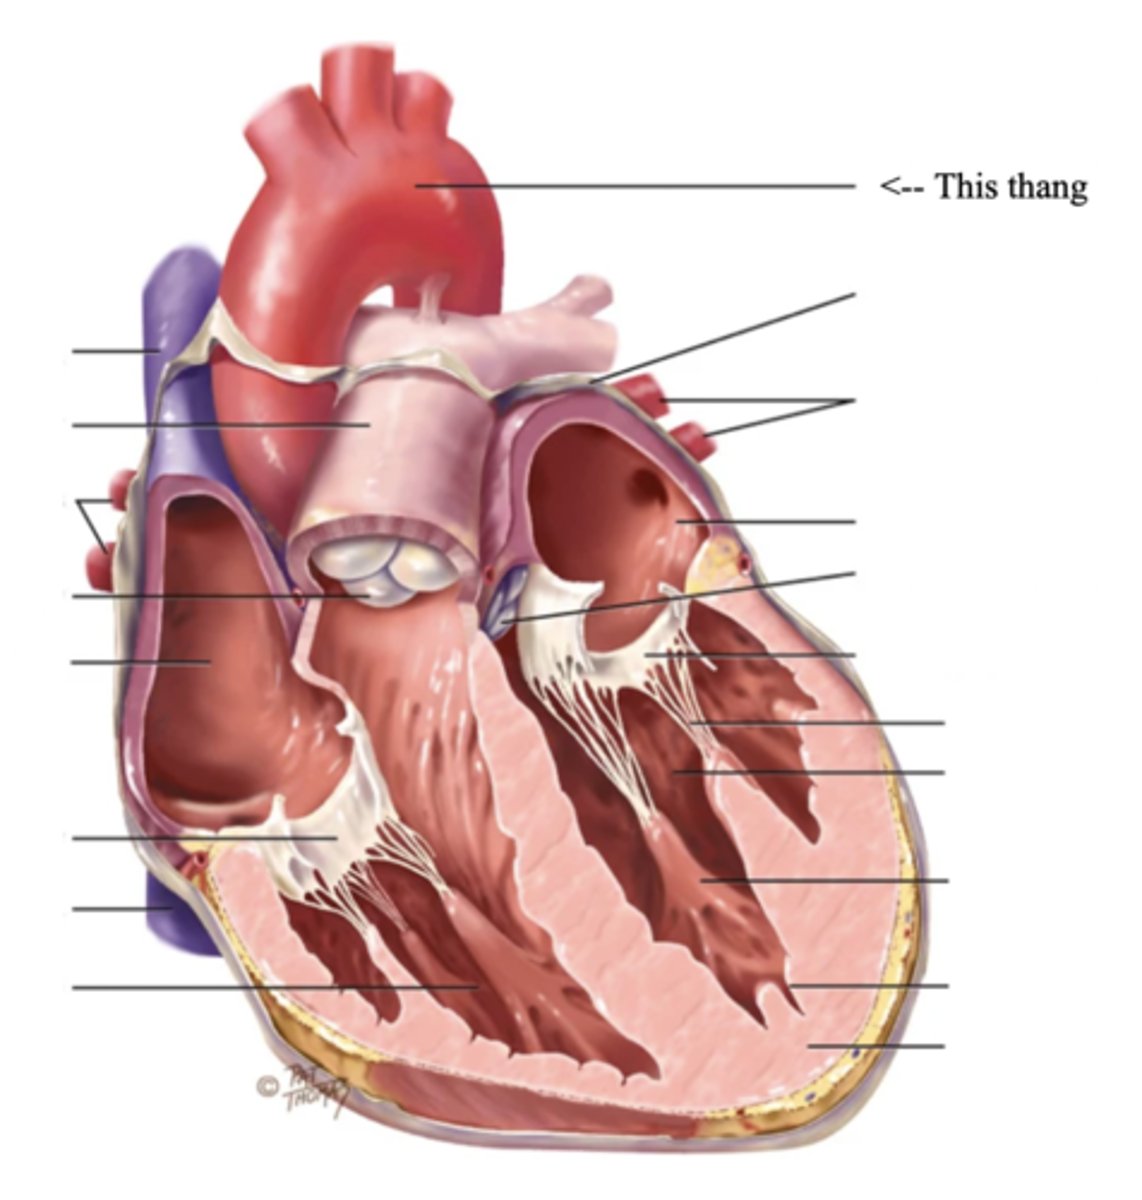

Anatomy of the Heart

2 Types of Chambers in the Heart

- Atrium

- Ventricles

Atrium (2)

A thin-walled reservoir for holding blood, located at the upper chamber of the heart

Ventricle (2)

The thick walled muscular pumping chamber of the heart located at the bottom chamber of the heart

2 Main Types of Valves of the Heart

- Atrioventicular

- Semilunar

Atrioventricular Valves (AV) (2)

The valves that separate the atria and the ventricles

The 2 Atrioventicular Valves of the Heart

- Tricuspid

- Mitral

Tricuspid Valve

- The right AV valve separating the right atrium from the right ventricle

- Connected by 3 chordae tendinae

Mitral (Bicuspid) Valve

- The left AV valve separating the left atrium from the left ventricle

- Connected by 2 chordae tendinae

Chordae Tendinae

Fibers (heart strings) attatched to the tricuspid and mitral valve which pull it closed when papillary muscles contract, preventing back flow of blood

Semilunar Valves (SV) (2)

Valves located between the ventricles and the pulmonary arteries and aorta

The 2 Semilunar Valves of the Heart

- Pulmonic

- Aortic

Pulmonic Valve

The SV valve of the right side of the heart

Aortic Valve

The SV valve of the left side of the heart

The 4 Great Vessels of the Heart

- Superior/inferior venae cavae

- Pulmonary artery

- Pulmonary veins

- Aorta

Superior/Inferior Venae Cavae

The large veins that empty into the right atrium of the heart and return unoxygenated venous blood to the right side of the heart

Pulmonary Artery

Artery carrying oxygen-poor blood from the heart to the lungs

Pulmonary Veins

Veins carrying oxygenated blood from the lungs to the heart

Aorta

The largest artery in the body which carries oxygenated blood from the heart throughout the body